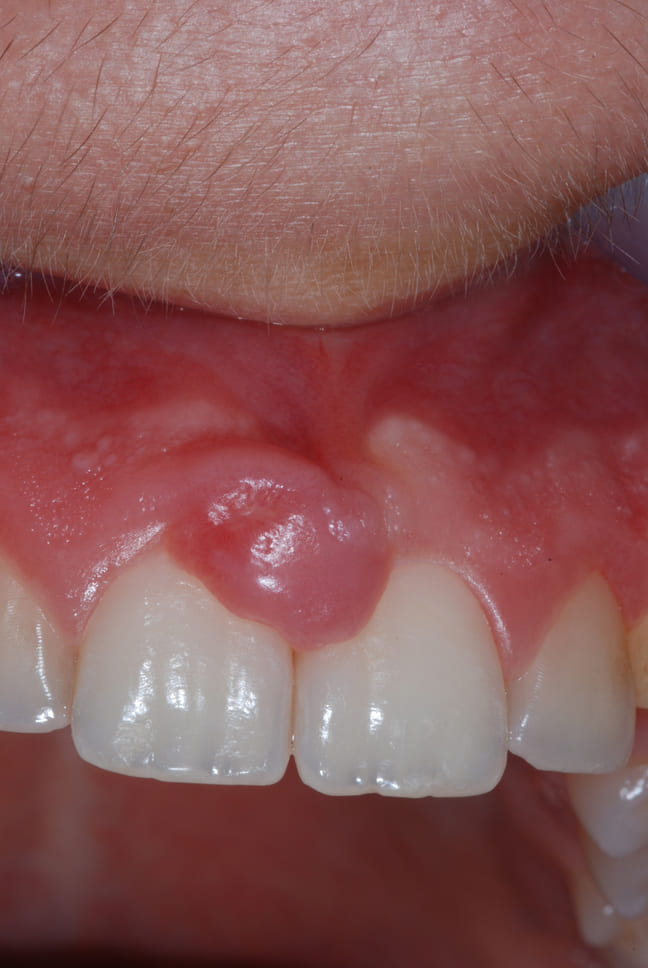

BlogDenti e gravidanza

Gravidanza: ormoni, epulide e sanguinamento gengivale